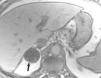

La aparición de nódulos suprarrenales se da en más del 10% de los pacientes con cáncer de pulmón. Dada la elevada frecuencia de adenomas benignos, es crucial la distinción entre éstos y la afectación metastásica. Ésta se puede llevar a cabo con una combinación de estrategias de imagen que incluyen TC, RM y/o PET. Por TC los adenomas suprarrenales típicamente tienen valores de atenuación bajos por la presencia de cúmulos lipídicos. Una lesión suprarrenal con valores de atenuación menores de 10 unidades Hounsfield (UH) en el estudio sin contraste, tiene una probabilidad del 98% de que se trate de una lesión benigna. Dado que ambas lesiones, adenomas y metástasis captan contraste, la valoración rutinaria de la captación no es útil en la diferenciación entre benignidad y malignidad. Si se detecta durante la realización de la TC, realizar cortes tardíos a los 15 minutos de la administración de contraste es importante, ya que si existe un lavado del contraste de más del 50% el diagnóstico de adenoma tiene una sensibilidad del 98% y una especificidad que oscila entre el 92 y el 100%20. La RM con secuencias de desplazamiento químico en la valoración de nódulos suprarrenales tiene una especificidad del 100% para el diagnóstico de adenoma (fig. 14). Sin embargo, la sensibilidad depende de la densidad de la lesión en el estudio con TC, ya que cuanto mayor es la densidad en la TC menos señal perderá en la RM, con lo que resulta más difícil etiquetarlo como adenoma21. La PET presenta una sensibilidad alta en la detección de metástasis suprarrenales, ya que cuando una lesión suprarrenal no muestra signos concluyentes en la TC de benignidad, la ausencia de actividad con la PET hace muy probable dicho diagnóstico. En los casos en que persistan dudas diagnósticas se debe recurrir a la biopsia de la lesión adrenal, especialmente si de este diagnóstico depende el manejo del paciente.

Fig. 14.--Lesión suprarrenal. (A) Tomografía computarizada (TC) abdominal sin contraste que muestra un nódulo suprarrenal derecho de baja atenuación y contornos bien definidos (flecha). (B) Con contraste se aprecia captación del mismo. (C) Resonancia magnética (RM) en fase en la que se identifica el nódulo suprarrenal isointenso con el hígado. (D) En la RM fuera de fase, se pone de manifiesto la pérdida de señal (marcadamente hipointensa con respecto al hígado) característica de estos tumores suprarrenales debido a su contenido lipídico.